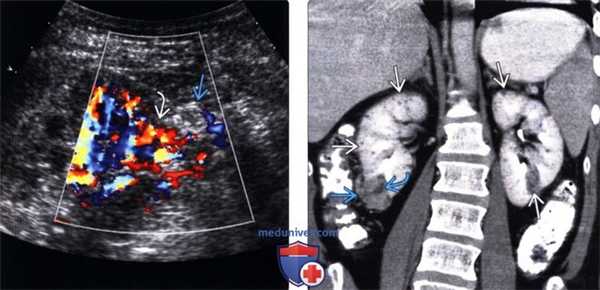

(Левый) На продольном УЗ срезе с цветовой допплерографией у этого же пациента с туберозным склерозом визуализируется экзофитная гиперэхогенная АМЛ. Кровоснабжение АМЛ происходит из переходных сосудов.

(Правый) Фронтальный КТ срез в отсроченную фазу контрастирования у пациента с туберозным склерозом, визуализируется экзофитная АМЛ, преимущественно солидная, с немногочисленными участками жировой клетчатки. Визуализируются также множественные другие АМЛ, с наиболее крупной в верхнем полюсе левой почки.

• Цветовая допплерография:

о Обнаружение псевдоаневризмы:

- Овоидные или округлые структуры, заполненные цветовым потоком, находящиеся внутри или рядом с АМЛ Цветовой поток имеет вид завихрения или в виде признака «инь-янь»

- Во время спектрального анализа шейки псевдоаневризмы обнаруживают классическую картину потока «из стороны в сторону»

• Энергетическая допплерография:

о Большинство АМЛ обладают «внутриопухолевой очаговой картиной»:

- Центральный внутренний поток, не распространяющийся к краям опухоли

о Напротив, большинство ПКР небольших размеров обладают смешанной периферической и проникающей картиной:

- Поток определяют в центре опухоли с распространением к ее краям/периферии

6. Ангиография:

• Опухоль с увеличенным сосудистым компонентом:

о Гиперваскулярное образование с неупорядоченными, длинными и извитыми сосудами о Мешковатые псевдоаневризмы

о Отсутствие артериовенозных шунтов

о Картина капиллярной нефрограммы в виде «солнечных лучей»

о Периферические сосуды в венозную фазу имеют вид «луковичной шелухи»